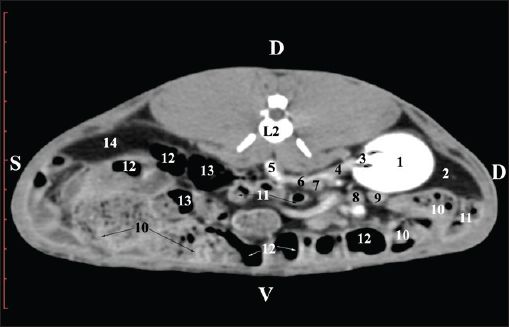

Fig. 4. Pre-contrast CT anatomical scan of the regio-abdominis media at the cranial L2 edge level. (1) Ren dexter; (2) pelvis renalis; (3) lobus caudatus (proc. caudatus) with visceral adipose tissue; (4) pars descendens of the duodenum; (5) ileum; (6) jejunum; (7) colon ascendens; (8) cecum; (9) colon transversum; (10) colon descendens; (11) lien; (12) pars transversa of the duodenum ; (*) ureter; (white arrow) recessus renalis.

Fig. 5. Pre-contrast computed tomography (CT) anatomical scan of the regio-abdominis media at the caudal L2 edge level. (1) Ren dexter; (2) pelvis renalis; (3) lobus caudatus (proc. caudatus) with visceral adipose tissue; (4) gl. adrenalis dextra; (5) ileum; (6) jejunum; (7) colon ascendens; (8) cecum; (9) colon transversum; (10) colon descendens; (11) lien; (*) ureter; (white arrow) recessus renalis. At the L3 level, the anatomical adjacencies of the right kidney with the pars descendens of the duodenum, ileum, cecum, and colon descendens were visualized. Hypoattenuated right ureter and normoattenuated gl. adrenalis dextra were situated medially to the right kidney. Extremitas caudalis of the right kidney was a clearly visible normoattenuated finding, surrounded by hypoattenuated borders of abdominal adipose collections (Figs. 6 and 7).